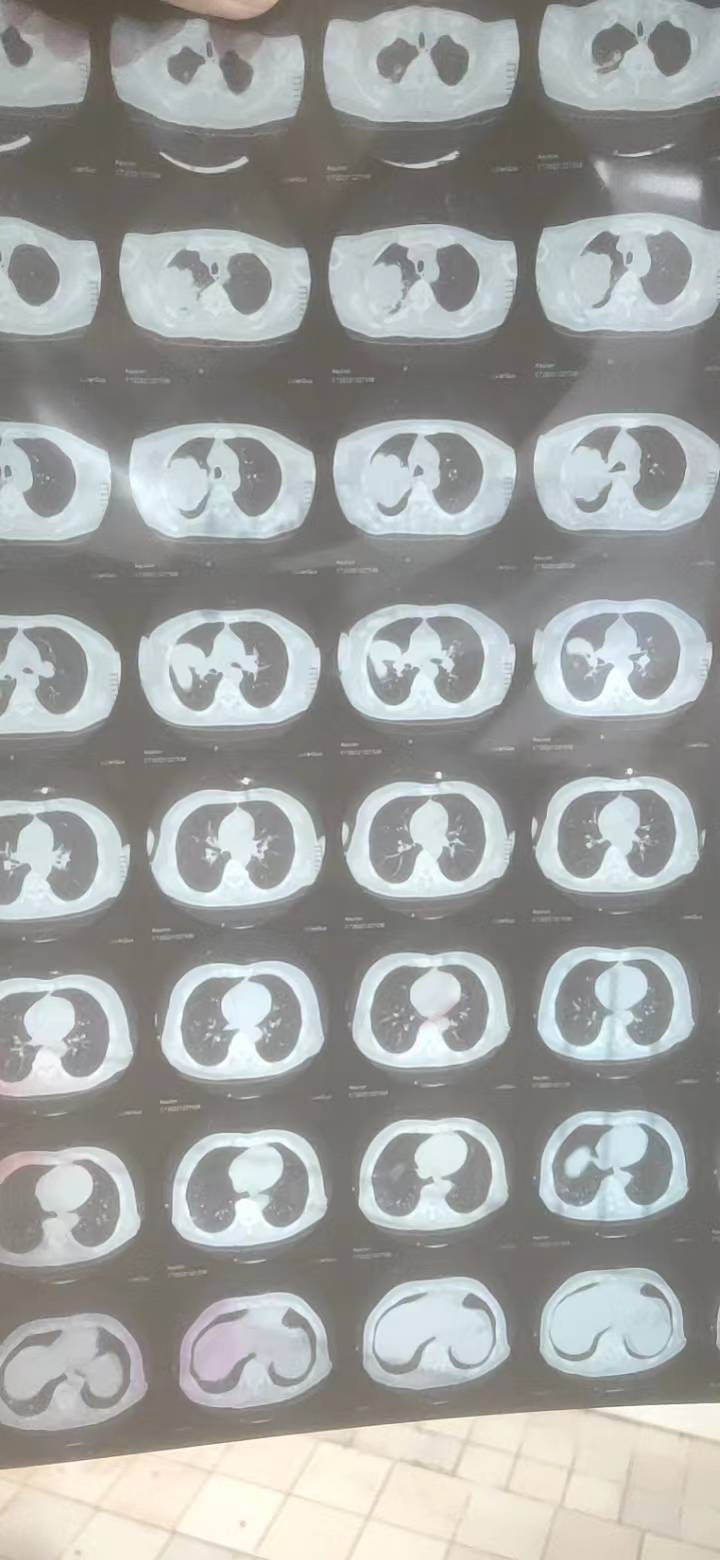

手术目前就不用考虑了,至少是3期了,还是寻求化疗和靶向治疗

局部晚期,有转移了肯定不能直接手术了,一般可以这样理解,就是气管镜够得到的话就是中央型(当然有些情况是肿瘤太大可以够到,但是实际附着区域可能在周围?),血管分布就是从心脏大血管向两肺分支,可以去搜下肺血管的解剖图,结合肿瘤部位自行想象这个距离(这么大的肿瘤一般都靠近大血管的,很考验外科医生的水平